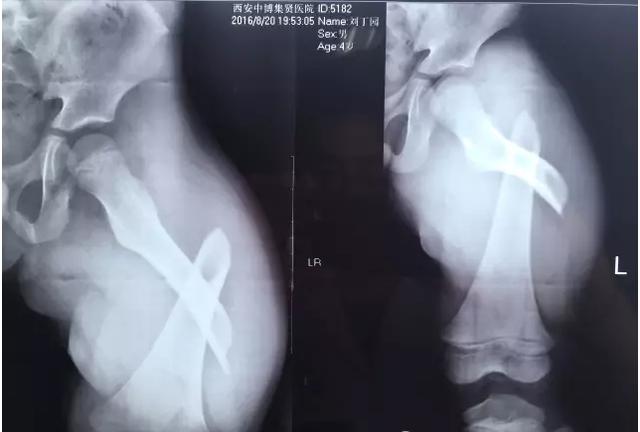

专家表示,大部分骨折是跌倒引起的,最多见的就是骨质疏松性骨折,主要包括桡骨远端、肱骨近端、胸腰椎骨折和髋部骨折。

“许多人跌倒后的第一反应是手撑地,导致摔倒的力量经手腕传导至前臂,从而形成桡骨远端骨折。”北京积水潭医院新街口院区创伤骨科副主任医师王陶说,如果是髋部骨折,对高龄老人而言,风险和危害更大。